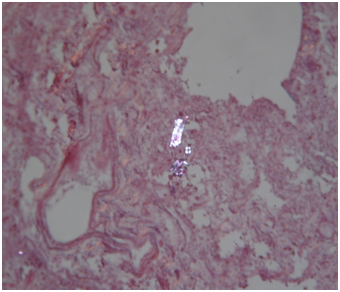

Histology: Acute emphysema was the prominent observation; edema and hemorrhages were also present.4 In 9 cases (Figures 3-6), exogenous material in the airways, comprehensive of planktonic boli in the lower branches, clearly demonstrable at polarization microscope (and possibly confirmable at SEM’s elemental analysis with EXD). Zoo- and phytoplankton have been better identified in the UV microscope. It is mandatory to differentiate the planktonic material from gastric content, regurgitated and aspirated (Figure 7 & 8).

Figure 5 Drowning in freshwater; recovery corpse in the sea after 20 days. Endoalveolar phyto- and geoplankton (EE, 240X, polarized light).